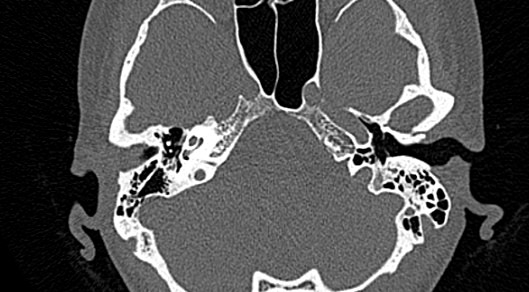

Мультиспиральная КТ позволяет детально визуализировать все вышеперечисленные анатомические структуры височных костей, диагностировать заболевания среднего и внутреннего уха.

КТ наиболее информативна при черепно-мозговых травмах, воспалительных заболеваниях уха, опухолевых процессах этой области. При компьютерной томографии возможно проследить ход барабанной перепонки, оценить структурность и положение слуховых косточек (молоточка, стремечка и наковальни), оценить объем и расположение содержимого в антральной клетке или ячейках сосцевидного отростка височной кости.

- показать четкую картину строения среднего уха.